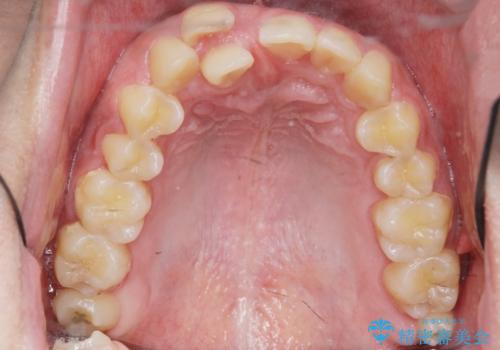

正中過剰埋伏歯で生じた前歯の審美障害 矯正治療での改善

- 前歯の見た目に悩まれて来院されました。

当初他院では、抜歯を行いセラミックブリッジを提案されていましたが、他の方法はないかと総合歯科治療を行う当院へと相談来院されました。

「時間がかかっても良いので、できれば歯を抜かずに矯正治療で治したい。」という強い希望があったので、矯正治療で歯並び・審美性の改善を計画します。

見た目、噛み合わせが大きく改善し、大変喜んでいただくことができました。